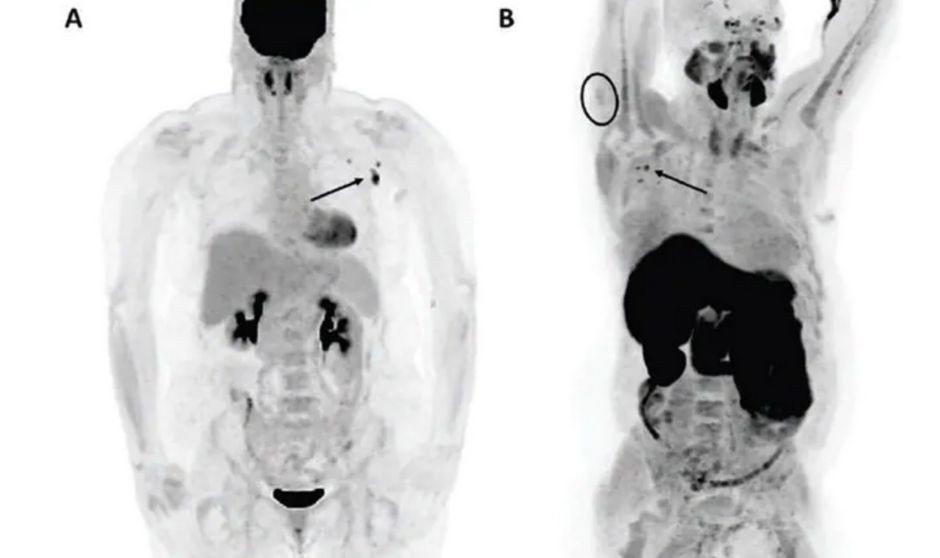

Imagen de tomografía tras vacuna Covid-19.

Las vacunas contra el Covid de ARN mensajero (Pfizer/BioNTech y de Moderna) pueden “desencadenar linfadenopatía reactiva y captación de radiotrazador en las imágenes de tomografía por emisión de positrones/tomografía computarizada (PET-CT), lo que confunde la interpretación de las imágenes y con ello dar lugar a falsos positivos”, han explicado los investigadores.

En cuanto a los datos que ha arrojado el estudio, siete de 67 pacientes con cáncer (10,4 por ciento) tuvieron captación de radiotrazador en los ganglios linfáticos axilares en las imágenes de tomografía por emisión de positrones/tomografía computarizada, dentro de los 24 días posteriores a la vacunación. Incluidos cuatro con captación de fluorodesoxiglucosa-F-18 y tres con captación de colina.

Un paciente presentó captación ganglionar extraaxilar (captación supraclavicular ipsolateral en la PET con FDG). La captación deltoidea ipsolateral estuvo presente en el 14,5 por ciento (8/55) de los pacientes con lateralidad de la inyección documentada, incluido el 42,9 por ciento (3/7) de los pacientes con ganglios linfáticos axilares positivos.

Los investigadores han concluido que "ocasionalmente se observa un aumento de la captación de los ganglios linfáticos axilares o deltoides ipsilateral en la PET con FDG o 11C-colina realizada después de la vacunación con Pfizer-BioNTech o Moderna". En este contexto, sugieren que "los médicos intérpretes deben reconocer las características de la captación anormal en la PET después de la vacunación para guiar el manejo de seguimiento óptimo y reducir las biopsias innecesarias".